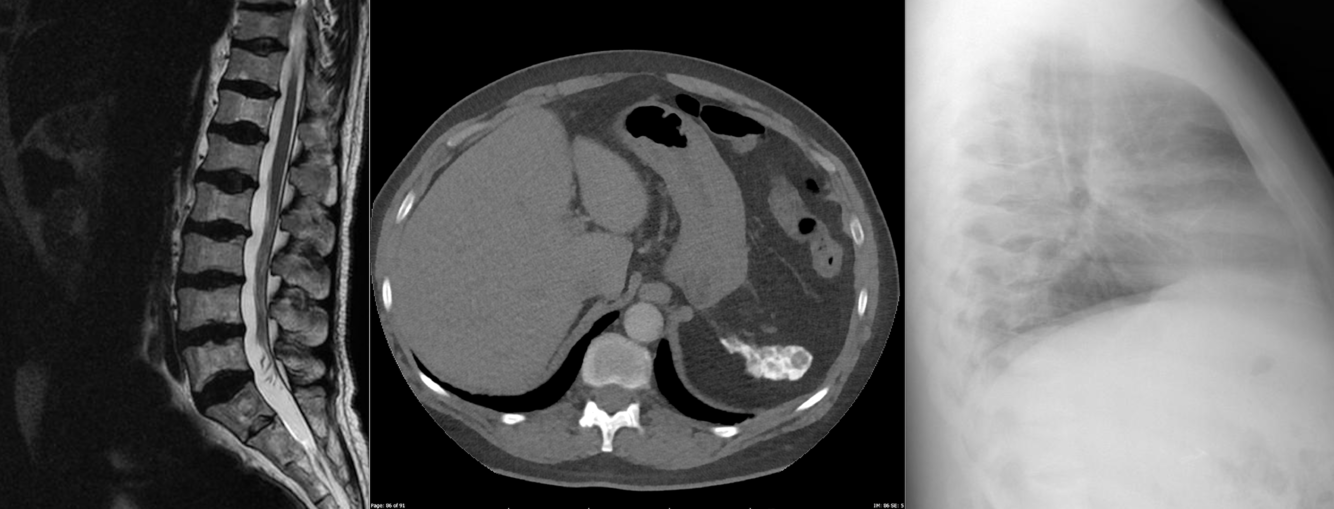

In the left upper quadrant, anterior to the renal pelvis, is a focal region of mural thickening with consistent (in a patient with known Lynch syndrome) with a DJ flexure adenocarcinoma. Note the previous colectomy.

Case Discussion

This patient has known Lynch syndrome and has had prophylactic colectomy.

Presents with DJ flexure adenocarcinoma, confirmed at laparotomy.